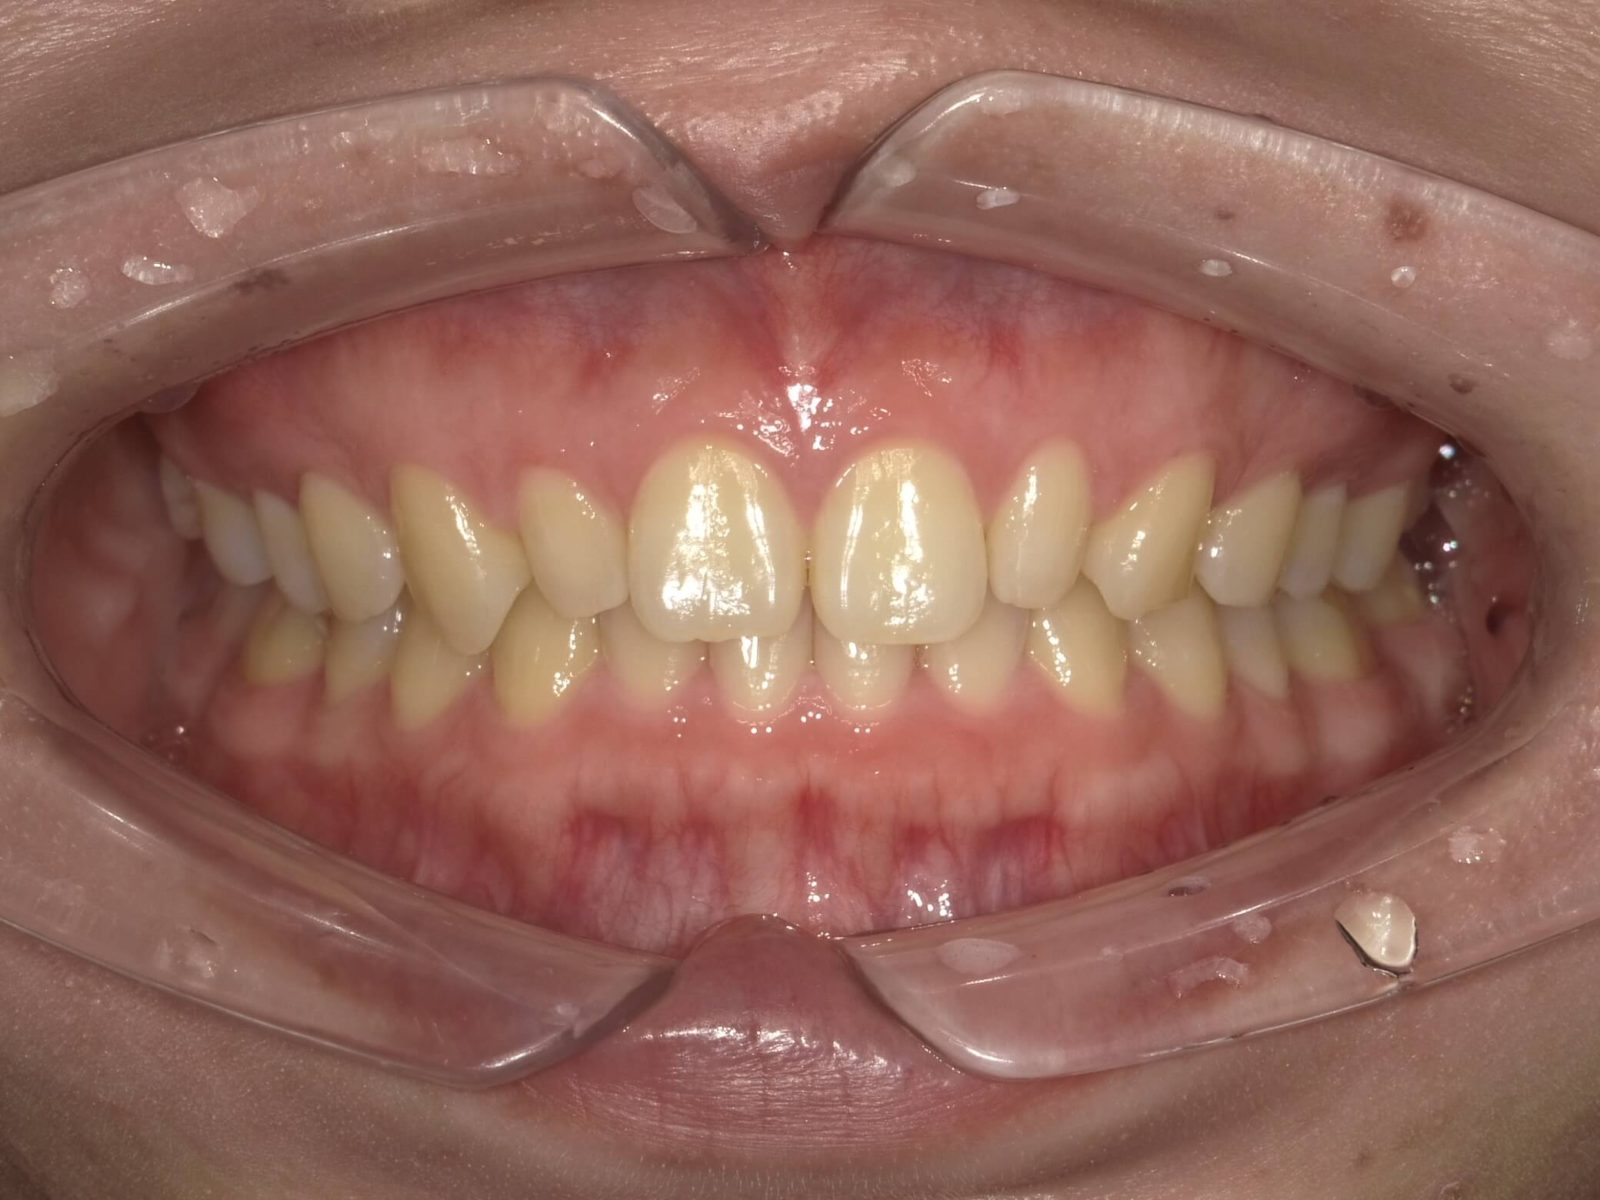

• 治療前

• 治療後